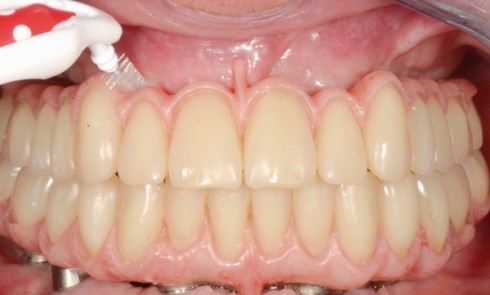

Article réservé à nos abonnés Piézographie : technique de choix dans la prise en charge des crêtes plates et négatives mandibulaires

Le praticien reçoit fréquemment en consultation des patients édentés totaux ayant des crêtes mandibulaires plates ou négatives avec tous les...